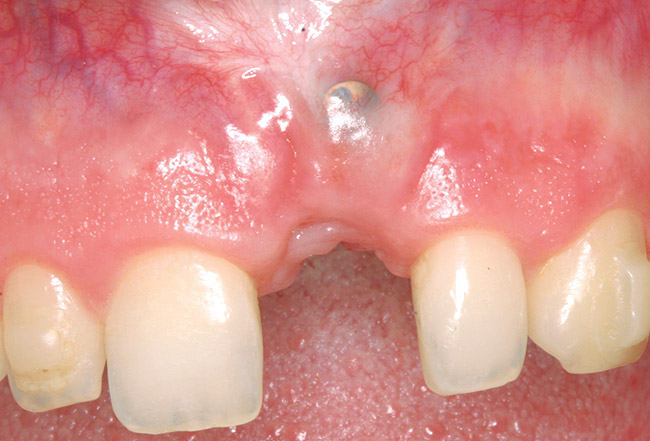

A 39-year-old woman presented with a failing endodontically treated maxillary right central incisor. Clinical and radiographic examination revealed a thick, flat periodontal biotype, high smile line, and a fistulous tract of the labial vestibule opposite the incisor (Figure 16 and Figure 17). Also noted post-extraction was a thin (< 2 mm) labial plate with 8 mm of vertical bone loss (Figure 18). Treatment consisted of a conservative flapless extraction with placement of a free connective tissue graft (Figure 19) sutured through the socket, along with placement of a bone mineralized allograft (MinerOss) (Figure 20 and Figure 21). Five months post-extraction, a root-form implant was placed, nonsubmerged, along with a bovine bone xenograft as a veneer into a sub-periosteal labial pouch (Figure 22 through Figure 24). A provisional crown was placed 3 months later, allowing for adequate soft-tissue grooming (Figure 25).

Figure 18  Post-extraction socket defect with loss of labial plate.

Figure 18